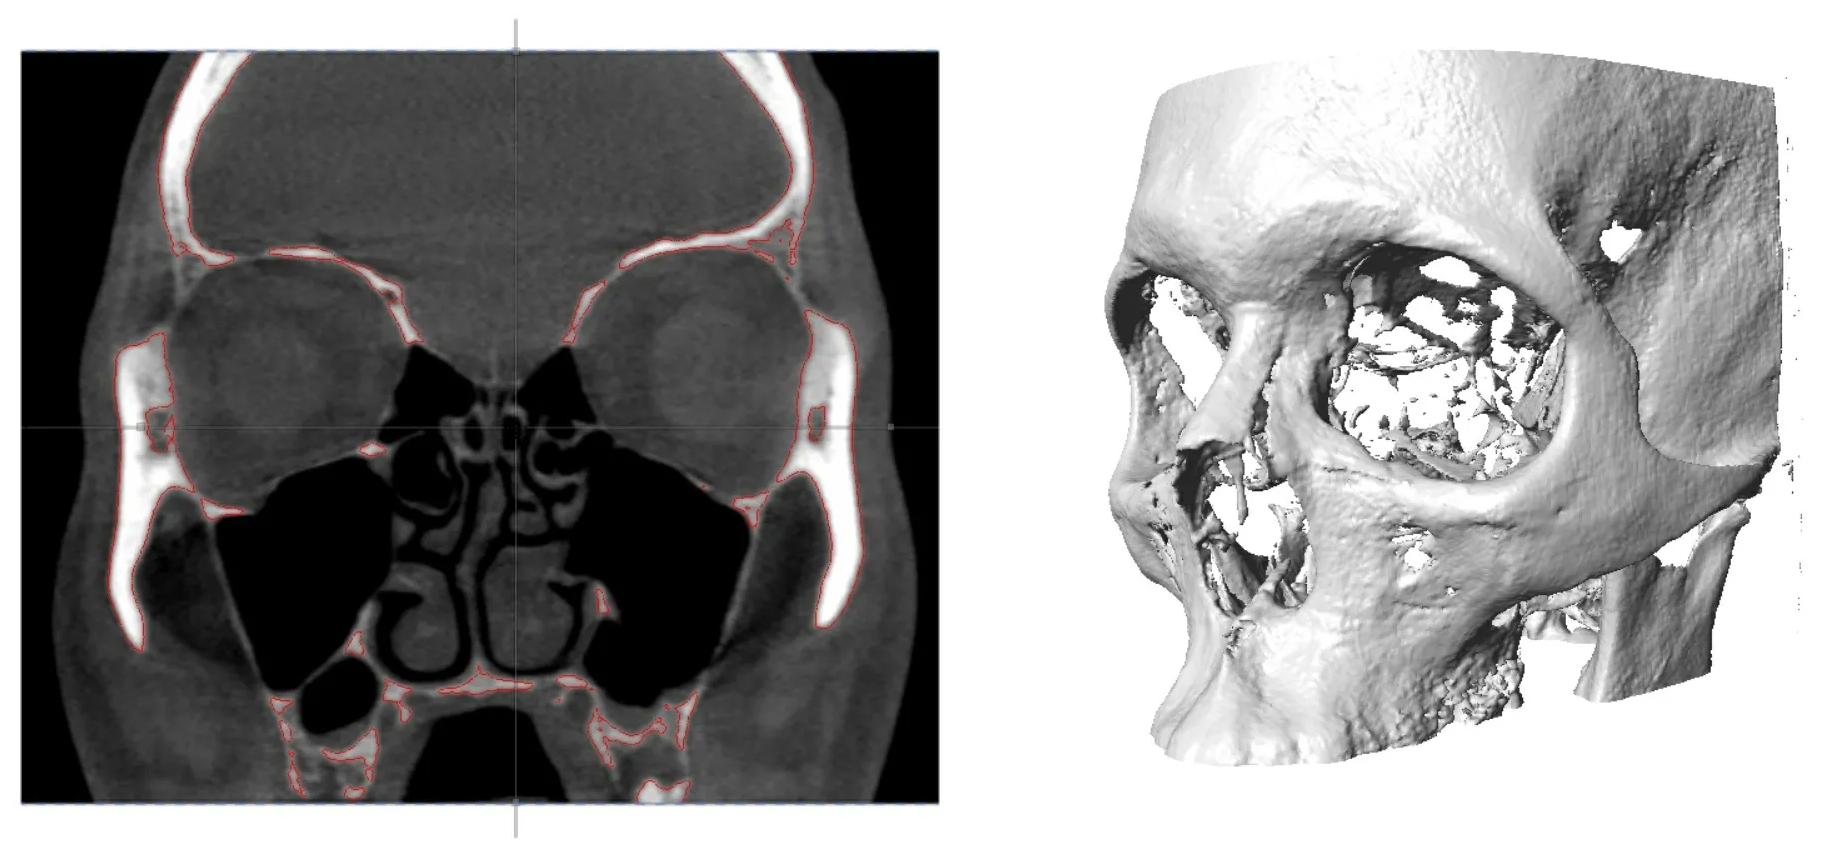

Active Landmark Placement on Human Skull

• Forensics: Checkpoint's landmark placement and analysis tools are invaluable in forensic anthropology for reconstructing faces from skeletal remains. By placing landmarks at key anatomical points, forensic experts can infer the soft tissue depth and reconstruct features for identification purposes. In forensic engineering, landmarks can help in the analysis of fracture patterns or deformation in materials to understand the sequence of failures.

• Example Project: Forensic anthropologists use Checkpoint to place landmarks on a skull's surface, guiding the facial reconstruction process for unidentified remains.